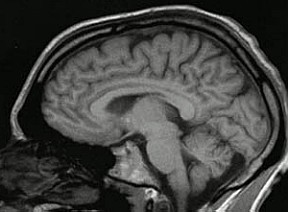

Qual seria a resposta à estimulação cerebral profunda (DBS, na sigla em inglês) em regiões específicas do cérebro de pacientes com sintomas de depressão? Essa estimulação modificaria a resposta em animais experimentais induzidos a estresse? Quais seriam as alterações relacionadas aos hormônios produzidos na região do hipotálamo e na hipófise?

Essas são perguntas que os pesquisadores Luciene Covolan, da Universidade Federal de São Paulo (Unifesp), em São Paulo, e Clement Hamani, professor de neurocirurgia da Universidade de Toronto, no Canadá, pretendem responder durante um projeto de pesquisa desenvolvido em cooperação por meio do acordo firmado em 2011 entre a FAPESP e a universidade canadense.